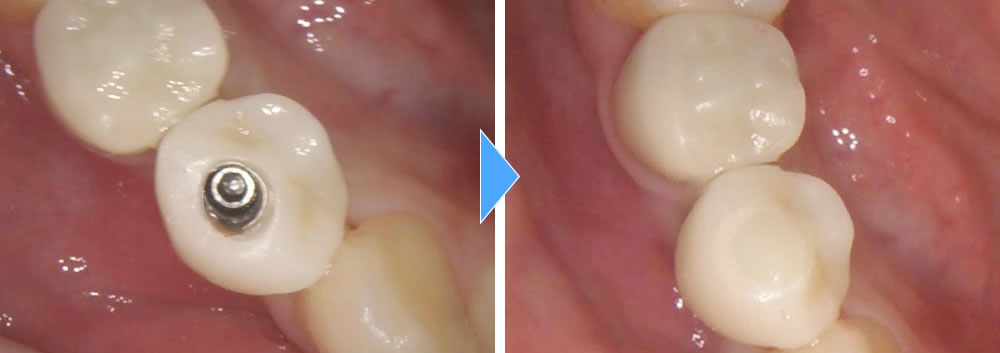

| 費用 | CT検査 0円 骨造成 88,000円 インプラント治療(上部ジルコニア含め)429,000円 |

そこから4ヵ月間の待機後、しっかりと骨とインプラント体が結合している事を確認し、上部の歯を使っていきました。結果、咬合も回復し、綺麗な歯を作る事ができました。